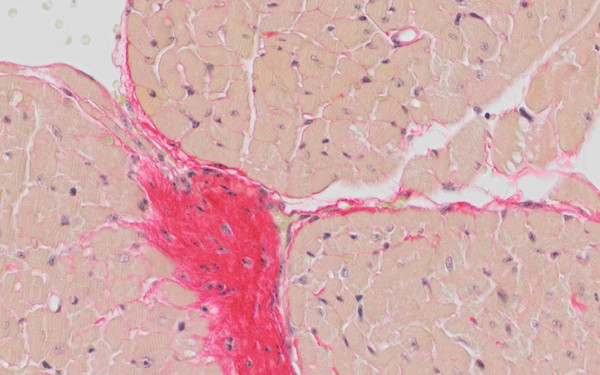

Stressed vessels in progeria

LMNA mutations cause progeria, a severe disease with features of accelerating aging in multiple tissues, including cardiovascular disease and atherosclerosis. We show that vascular endothelial cells in progeria cannot cope with blood flow-mediated shear stress and upregulate pro-fibrotic mechanosignaling pathways, causing fibrosis, vessel stiffening and heart problems.